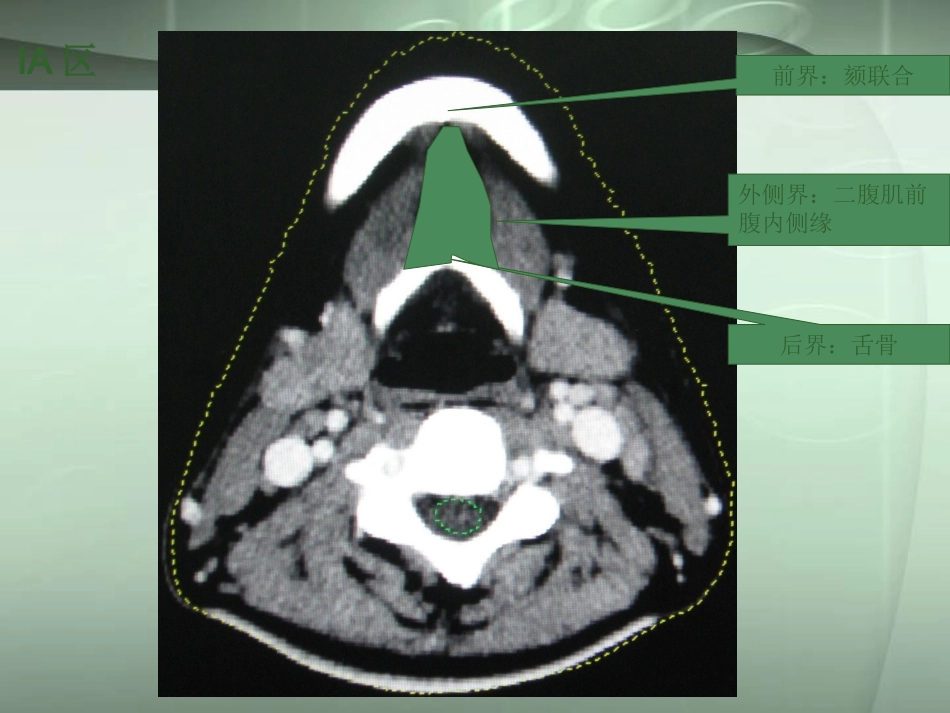

颈部淋巴结分区及转移特征颈部淋巴结分区及转移特征前界:颏联合外侧界:二腹肌前腹内侧缘后界:舌骨IA区Ⅰa区是一个位于中央的三角形区域,包括颏下淋巴结。是口底、舌前、下颌骨前牙槽突和下唇肿瘤发生隐匿性转移的高危区域。ⅠⅠaa区区下颌舌骨肌后界:颌下腺后缘内侧界:二腹肌前腹外侧缘外侧界:下颌骨内缘、颈阔肌前界:下颌骨前缘IB区Ⅰb区包括下颌下淋巴结,口腔、前鼻腔、面中部软组织和下颌下腺肿瘤易发生这一区域淋巴结转移。Ⅰb区II区外侧界:胸锁乳突肌内缘后界:胸锁乳突肌后缘内侧界:颈部血管鞘内缘和肩胛提肌前界:颌下腺后缘、颈部血管鞘前缘Ⅱ区包括颈静脉上组淋巴结,是鼻腔、口腔、咽、喉和涎腺肿瘤发生隐匿转移的高危区域,与口咽或鼻咽的肿瘤关系更为密切。颈内静脉周围淋巴结颈内静脉后方淋巴结前界:胸锁乳突肌前内缘后界:胸锁乳突肌后缘内侧界:颈部血管鞘内缘和棘旁肌外侧界:胸锁乳突肌内缘III区Ⅲ区包括颈静脉中组淋巴结,是口腔、鼻咽、口咽、下咽和喉肿瘤发生隐匿性转移的高危区域。前界:胸锁乳突肌前内缘后界:胸锁乳突肌后缘内侧界:颈部血管鞘内缘和棘旁肌外侧界:胸锁乳突肌内缘IV区Ⅳ区包括颈静脉下组淋巴结,是下咽、喉和颈段食管肿瘤发生隐匿性转移的高危区域。前界:胸锁乳突肌后缘后界:斜方肌前侧缘内侧界:肩胛提肌外侧界:颈阔肌和皮肤V区Ⅴ区包括颈后三角淋巴结群。是鼻咽、口咽、声门下喉、梨状窝顶、颈段食管和甲状腺肿瘤发生隐匿性转移的高危区。VI区后界:气管和食管分界处前界:颈阔肌和皮肤外界:胸锁乳突肌前外缘、皮肤和甲状腺内缘Ⅵ区,亦称颈前间隙,包括喉前、气管前和气管旁淋巴结及甲状腺周围淋巴结。是甲状腺、声门和声门下喉、梨状窝顶和颈段食管肿瘤发生隐匿性转移的高危区域。咽后淋巴结外侧界:颈内动脉内缘后界:头长肌前界:腭帆提肌咽后淋巴结:原发或侵犯枕部粘膜和颈部器官如鼻咽、咽壁和软腭等部位的肿瘤易发生咽后淋巴结转移。对于咽部肿瘤,当其它区域淋巴结转移阳性时,更易发生咽后淋巴结转移。颈部淋巴结转移颈部淋巴结转移甲状腺癌转移淋巴结多为单侧发生,常见于Ⅲ、Ⅳ区,尤其可发生气管食管沟及上纵隔淋巴结移,而头颈部其他原发肿瘤很少转移至此。前界:胸锁乳突肌前内缘后界:胸锁乳突肌后缘内侧界:颈部血管鞘内缘和棘旁肌外侧界:胸锁乳突肌内缘III区前界:胸锁乳突肌前内缘后界:胸锁乳突肌后缘内侧界:颈部血管鞘内缘和棘旁肌外侧界:胸锁乳突肌内缘IV区VI区后界:气管和食管分界处前界:颈阔肌和皮肤外界:胸锁乳突肌前外缘、皮肤和甲状腺内缘转移淋巴结形态及边缘转移淋巴结形态及边缘表现为形态规则且边缘清楚与形态不规则且边缘不清楚者,其原发肿瘤之间存在极显著性差异。鼻咽癌及甲状腺癌转移淋巴结边界多较清。口咽癌,喉癌及下咽癌边界多不清,且外侵明显。这与口咽癌、下咽癌及喉癌分化差,恶性程度高有关。淋巴结的密度及内部结构淋巴结的密度及内部结构不规则环形强化伴中央低密度为鳞癌转移淋巴结的CT特征性表现。CT图像所见中心低密度区,为肿瘤坏死、角蛋白、纤维组织、间质积液或水肿及存活的瘤细胞共同构成。淋巴结的密度及内部结构淋巴结的密度及内部结构甲状腺癌转移淋巴结血供丰富,且有甲状腺组织的吸碘特性,故强化明显,密度与正常甲状腺或甲状腺肿瘤相仿。颈部淋巴结转移的诊断标准颈部淋巴结转移的诊断标准①横断面图像上淋巴结最小径≥10mm;②中央坏死或环形强化;③同一区域内3个或以上的淋巴结呈簇状聚集且最小径≥8mm;④淋巴结包膜外侵犯(征象包括淋巴结;边缘不规则强化,周围脂肪间隙部分或全部消失,淋巴结相互融合);⑤咽后淋巴结横断面最小径>4mm,如转移咽后淋巴结与原发灶任何一层面均无法区分者归为原发灶。鉴别诊断鉴别诊断淋巴瘤,以非霍奇金淋巴瘤多见。典型的CT表现为双侧性、多发淋巴结肿大,直径约3~10cm,密度多均匀,仅非霍奇金淋巴瘤偶见中心坏死。感染性病变常为邻近间隙的化脓菌或结核菌感染侵及颈深淋巴链所致。临床表现为伴感染症状的颈部压痛性肿块。CT上显示病变范围大,边缘模糊,脓肿形成后可为边缘强化的囊性结构影。鉴别诊断鉴别诊断颈部淋巴结肿大,约1...